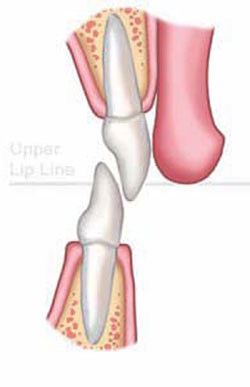

Perhaps one of the most common yet complex cases involves severe wear of the incisal edges of anterior teeth. When a parafunctional habit exists,4 incisal wear develops to varying degrees depending on the malocclusion (Figure 1A) and the patient’s age. Accompanying the wear is the often underappreciated dentoalveolar extrusion of the teeth,5 resulting in short and unesthetic anterior teeth with irregular gingival margins (Figure 1B). Often, these cases are treated by crown lengthening and restoration only, which is a compromised treatment plan. It requires unnecessary removal of vital soft and hard tissue and creates greater risks of damage to the pulpal tissues during final preparations.6 However, treating the fundamental problems requires the orthodontic intrusion5 of the anterior dentogingival complex (Figure 1C) and subsequent restoration of the lost tooth structure5 (Figure 1D). Leveling the gingiva can serve as an initial guide7 for the orthodontist. However, until the correct incisal edges are in place, he or she cannot accurately predict how the teeth relate to the lips when smiling, nor how the tooth form relates to the envelope of function4 as orthodontics is finalized (Figure 1E). In addition, the patient may not appreciate the unsightly “disappearance” of the remaining tooth structure, if teeth are intruded significantly during the orthodontic process (Figure 1C). Options for addressing these problems include preparation of the teeth and placement of provisional crowns (represents aggressive therapy and is prone to maintenance problems); composite-resin bonding (a very conservative treatment);8 or no restorative treatment at this stage. Because bonded-porcelain restorations preserve more tooth structure as compared with conventional metal-ceramic crowns, they are preferred as final restorations in most cases; therefore, conservation of tooth structure at this stage is most desirable.6

Adding the incisal edges in composite resin during orthodontic treatment seems an obvious and proven solution. This form of “trial therapy”4 is traditionally performed with the brackets in place and the wire removed by the “free-hand” placement of composite resin. Likely reasons that this is not more common may be ascribed to the level of difficulty involved and the amount of time required in placing direct composites in the esthetic zone. Also, the dentist may hesitate to increase costs to the patient who is already anticipating a substantial investment in final restoration. A simpler and less time-consuming method can be employed in which a wax-up is performed on a diagnostic model1 and a clear vinyl polysiloxane (VPS) matrix is used to direct warmed composite resin onto the teeth.9 The latter method serves well by reducing chair-time for the dentist and lowering cost to the patient; and the immediate improvement in the smile can be dramatic. In the authors’ experience, patient responses have been overwhelmingly positive. The orthodontist or restorative dentist can make modifications as needed to satisfy the esthetic or functional requirements of the case with the patient’s approval as final orthodontic movements are performed (Figure 1E).

Final porcelain restorations are placed only after adequate time has elapsed to allow settling of the teeth following bracket removal and healing of the gingival tissues. Intrusion cases may require up to 6 months of retention to achieve stable positions,7 and soft-tissue maturation may require an even greater length of time. The intermediate composite-resin restorations serve as the template for the final porcelain restorations, establishing proper incisal-edge position, emergence form, and functional occlusion,4 while maintaining optimal gingival health and esthetics. Ideal preparations can now be made with maximal conservation of tooth structure in mind to help ensure the longevity of the final restorations.6

Figure 1A Unwom initial malocclusion |  Figure 1B Dental wear with secondary dentoalveolar extrusion | ||||||

Figure 1C Orthodontic overcorrection |  Figure 1D Intermediate restoration to ideal anatomy (not function) | ||||||

Figure 1E Orthodontic finalization of esthetics and function | |||||||

| FIGURE 1A THROUGH FIGURE 1E Incisal wear with dentoalveolar extrusion. Note the relationship of the maxillary incisal edge to lip line. | |||||||